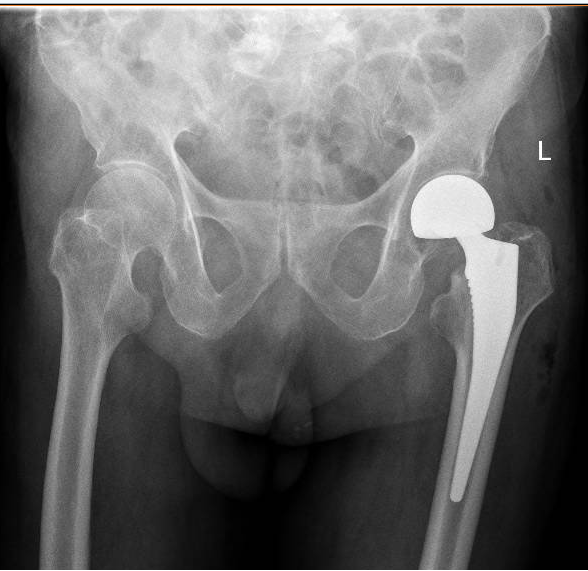

“王大爺入院時,檢查發(fā)現(xiàn)左側(cè)股骨頸骨折,也就是我們常說的‘髖關(guān)節(jié)骨折’。老人發(fā)生髖關(guān)節(jié)骨折,也被稱為‘人生最后一次骨折’,死亡率近60%。讓人痛心的是很多老人是死于骨折后長期臥床導(dǎo)致的并發(fā)癥?!笔兄嗅t(yī)醫(yī)院骨科主治醫(yī)師吳東海介紹,老人發(fā)生骨折后,如果采用保守治療,長期臥床容易發(fā)生壓力性損傷、尿路感染、肺部感染等并發(fā)癥,生活質(zhì)量幾乎無從談起,更有可能因并發(fā)癥威脅到生命。比較好的解決方案是盡快進(jìn)行手術(shù),讓老人重新站起來,減少并發(fā)癥的發(fā)生,提高生活質(zhì)量,也減輕家人的負(fù)擔(dān)。

“通過團(tuán)隊的默契配合,王大爺?shù)氖中g(shù)我們僅用30多分鐘就順利完成,術(shù)中出血量不到50ML,做到了手術(shù)時間少,出血少,把各種風(fēng)險降低到最小化。手術(shù)后,配合術(shù)后護(hù)理、內(nèi)科治療、中醫(yī)手法康復(fù)等,讓老人獲得了快速康復(fù)?!眳菛|海說,隨著技術(shù)的進(jìn)步,越來越多的高齡患者得益于先進(jìn)的綜合治療方法,這將讓更多的高齡患者提高生活質(zhì)量,重新煥發(fā)新活力。

骨傷三科重點專業(yè)技術(shù):髖、膝骨關(guān)節(jié)外科、運動醫(yī)學(xué)關(guān)節(jié)鏡技術(shù)等關(guān)節(jié)傷病的治療。以收治髖膝關(guān)節(jié)疾病和運動醫(yī)學(xué)(關(guān)節(jié)鏡)損傷治療為主的特色科室。主要是對髖、膝關(guān)節(jié)疾病如先天性髖關(guān)節(jié)復(fù)位、髖關(guān)節(jié)發(fā)育不良、股骨頸骨折、股骨頭壞死、股骨粗隆骨折、膝關(guān)節(jié)周圍骨折、髖膝關(guān)節(jié)炎、膝關(guān)節(jié)半月板、交叉韌帶損傷、肩踝運動損傷疾病等綜合治療,采用現(xiàn)代先進(jìn)理念和技術(shù)進(jìn)行股骨頭壞死早期控制、髖、膝關(guān)節(jié)置換、骨折的內(nèi)外固定等治療手段,幫助患者最快恢復(fù)健康。關(guān)節(jié)鏡??浦委煾鞣N關(guān)節(jié)疾病,如關(guān)節(jié)半月板損傷、膝關(guān)節(jié)叉韌帶斷裂,肩周炎、肩袖損傷、踝關(guān)節(jié)滑膜炎、關(guān)節(jié)游離體取出、關(guān)節(jié)軟骨損傷修復(fù)重建等。